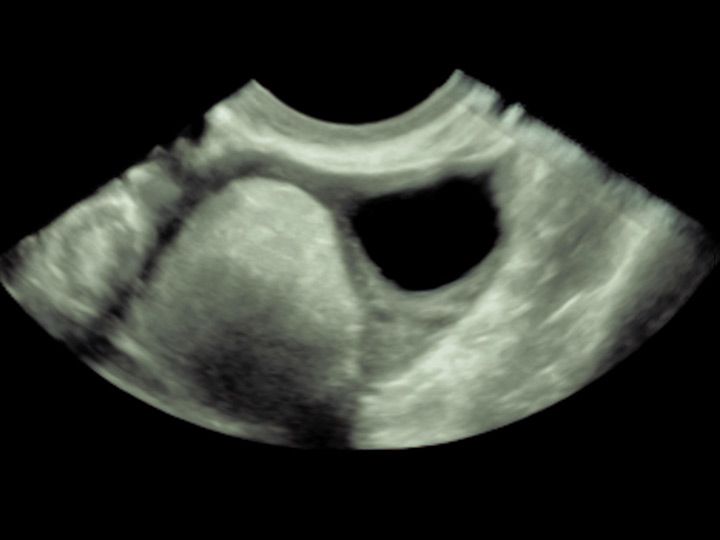

Dermoidzyste

Veränderungen des Eierstocks sind gerade vor den Wechseljahren häufig funktioneller Natur und durch zyklusbedingte Einflüsse zu erklären. Diese sollten nicht beunruhigen und sind in aller Regel im natürlichen Verlauf abzuwarten. Raumforderungen am Eierstock können aber auch Beschwerden hervorrufen. Zum anderen sollten sie gegen bösartige Veränderungen abgegrenzt werden. Letztere sind selten, jedoch von ungünstiger Prognose, wenn sie ein fortgeschrittenes Stadium erreicht haben.

Die Abgrenzung zwischen einer einfachen funktionellen Veränderung, einer gutartigen Veränderung oder einer potentiell bösartigen Veränderung sollte primär sonographisch erfolgen.